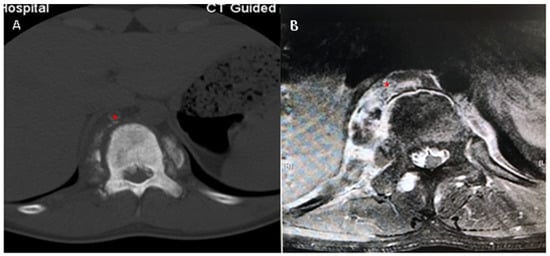

2. Case Report

3.2. Proactive Treatments Are Suggested for Azygos Vein with Tumor Thrombosis